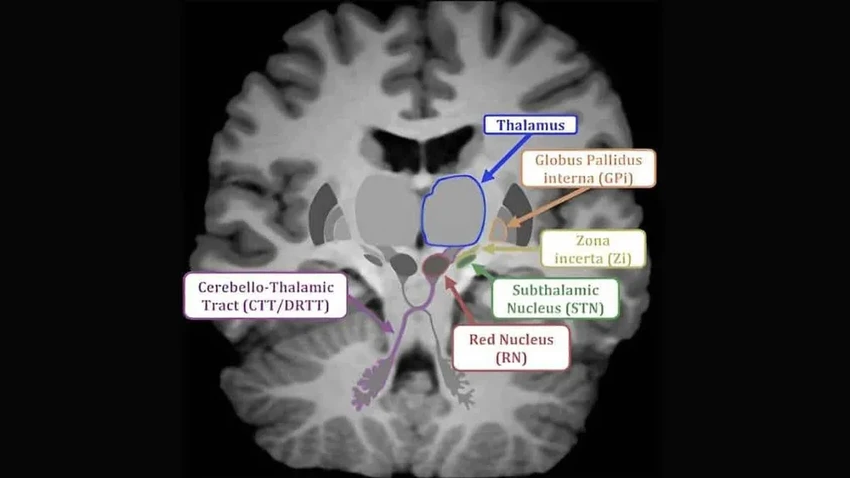

Марсело Дитрих и его команда внимательно наблюдали за мышатами в возрасте 16-18 дней. Используя методы визуализации в реальном времени, они зафиксировали активность в особой зоне мозга — zona incerta (ZI). Эта тонкая прослойка серого вещества под таламусом словно оживала, когда малыши взаимодействовали с матерью.

ZI — настоящий коммуникационный узел, обрабатывающий визуальные, слуховые и сенсорные сигналы. В раннем развитии она формирует множество связей, часть из которых сохраняется. Учёные обнаружили: при контакте с мамой у мышат активировались нейроны в ZI, вырабатывающие гормон соматостатин, известный своей ролью в регуляции множества процессов в организме.